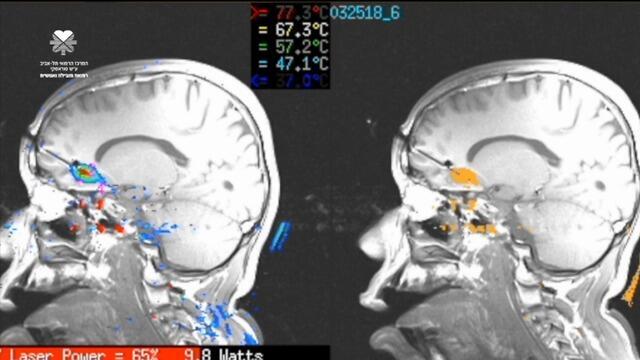

Врачи больницы "Ихилов" проводят операцию по прижиганию очага эпилепсии. Фото: Лиор Цур

Больному дают анестезию и осуществляют вмешательство под контролем прибора магнитно-резонансного сканирования (MRI). По катетеру передается лазерный луч, который выходит из его кончика и уничтожает патологический очаг, разогревая его до 60°С.

Для выявления очага в мозг Пелега ввели 80 электродов, с помощью которых отслеживали в течение 10 дней активность мозга. В ходе отслеживания снизили дозировку лекарств, чтобы спровоцировать приступ. Процедуру прижигания проводили д-р Идо Штраус, проф. Ицхак Фрид и д-р Орна Айзенштейн.